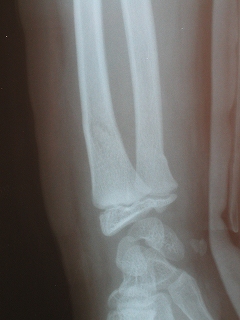

‰E‘O˜rœœÜ

@@”N—î@@8Î@—«

@@•‰“ú@•½¬14”N7ŒŽ27“ú

œÜÇ—á